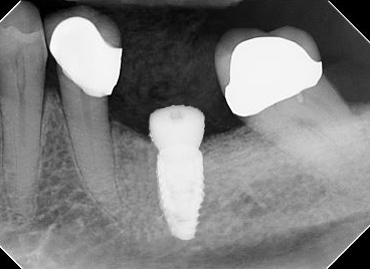

We take a comprehensive inside-out approach to your treatment. Beginning with photographic analysis of your overall smile, we may incorporate computer generated models of your mouth and/or digital radiographs of your underlying jawbone. From this digital information we can plan the position of your implants, and digitally fabricate the guide that will ensure your surgery goes exactly as planned.

• Digital radiographs and cone-beam computed tomography (CBCT) may be used to determine the health and level of bone which support your teeth. While the radiation dosage is significantly lower than film/analog radiographs which are no longer used in dentistry, we also make every attempt to ensure any radiation exposure is as low as reasonably achievable for diagnosis. Routine annual dental radiographs are 2-dimensional, whereas CBCT radiographs allow us to analyze structures 3-dimensionally, but are only taken as needed.